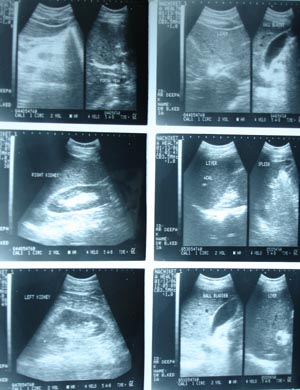

Ultrasonography whole abdomen

The routine USG for medicosurgical purpose is done in a systemic way of performance. Unless and until, specified about target organ the sonographer usually include all the structures of the abdomen. Start with liver in all planes, kidney in short & long axis, spleen, pancreas,vessels, particularly IVC & Aorta with any visible LN in any group.Bladder has to be full for evaluation of genitourinary tract.